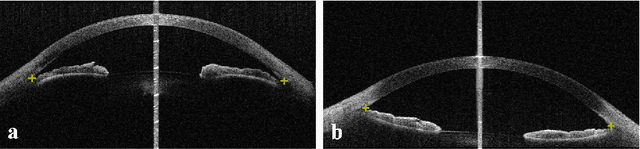

Abstract:Primary angle closure glaucoma (PACG) is the leading cause of irreversible blindness among Asian people. Early detection of PACG is essential, so as to provide timely treatment and minimize the vision loss. In the clinical practice, PACG is diagnosed by analyzing the angle between the cornea and iris with anterior segment optical coherence tomography (AS-OCT). The rapid development of deep learning technologies provides the feasibility of building a computer-aided system for the fast and accurate segmentation of cornea and iris tissues. However, the application of deep learning methods in the medical imaging field is still restricted by the lack of enough fully-annotated samples. In this paper, we propose a novel framework to segment the target tissues accurately for the AS-OCT images, by using the combination of weakly-annotated images (majority) and fully-annotated images (minority). The proposed framework consists of two models which provide reliable guidance for each other. In addition, uncertainty guided strategies are adopted to increase the accuracy and stability of the guidance. Detailed experiments on the publicly available AGE dataset demonstrate that the proposed framework outperforms the state-of-the-art semi-/weakly-supervised methods and has a comparable performance as the fully-supervised method. Therefore, the proposed method is demonstrated to be effective in exploiting information contained in the weakly-annotated images and has the capability to substantively relieve the annotation workload.

Abstract:Angle closure glaucoma (ACG) is a more aggressive disease than open-angle glaucoma, where the abnormal anatomical structures of the anterior chamber angle (ACA) may cause an elevated intraocular pressure and gradually leads to glaucomatous optic neuropathy and eventually to visual impairment and blindness. Anterior Segment Optical Coherence Tomography (AS-OCT) imaging provides a fast and contactless way to discriminate angle closure from open angle. Although many medical image analysis algorithms have been developed for glaucoma diagnosis, only a few studies have focused on AS-OCT imaging. In particular, there is no public AS-OCT dataset available for evaluating the existing methods in a uniform way, which limits the progress in the development of automated techniques for angle closure detection and assessment. To address this, we organized the Angle closure Glaucoma Evaluation challenge (AGE), held in conjunction with MICCAI 2019. The AGE challenge consisted of two tasks: scleral spur localization and angle closure classification. For this challenge, we released a large data of 4800 annotated AS-OCT images from 199 patients, and also proposed an evaluation framework to benchmark and compare different models. During the AGE challenge, over 200 teams registered online, and more than 1100 results were submitted for online evaluation. Finally, eight teams participated in the onsite challenge. In this paper, we summarize these eight onsite challenge methods and analyze their corresponding results in the two tasks. We further discuss limitations and future directions. In the AGE challenge, the top-performing approach had an average Euclidean Distance of 10 pixel in scleral spur localization, while in the task of angle closure classification, all the algorithms achieved the satisfactory performances, especially, 100% accuracy rate for top-two performances.

Abstract:Primary angle-closure disease (PACD) is a severe retinal disease, which might cause irreversible vision loss. In clinic, accurate identification of angle-closure and localization of the scleral spur's position on anterior segment optical coherence tomography (AS-OCT) is essential for the diagnosis of PACD. However, manual delineation might confine in low accuracy and low efficiency. In this paper, we propose an efficient and accurate end-to-end architecture for angle-closure classification and scleral spur localization. Specifically, we utilize a revised ResNet152 as our backbone to improve the accuracy of the angle-closure identification. For scleral spur localization, we adopt EfficientNet as encoder because of its powerful feature extraction potential. By combining the skip-connect module and pyramid pooling module, the network is able to collect semantic cues in feature maps from multiple dimensions and scales. Afterward, we propose a novel keypoint registration loss to constrain the model's attention to the intensity and location of the scleral spur area. Several experiments are extensively conducted to evaluate our method on the angle-closure glaucoma evaluation (AGE) Challenge dataset. The results show that our proposed architecture ranks the first place of the classification task on the test dataset and achieves the average Euclidean distance error of 12.00 pixels in the scleral spur localization task.